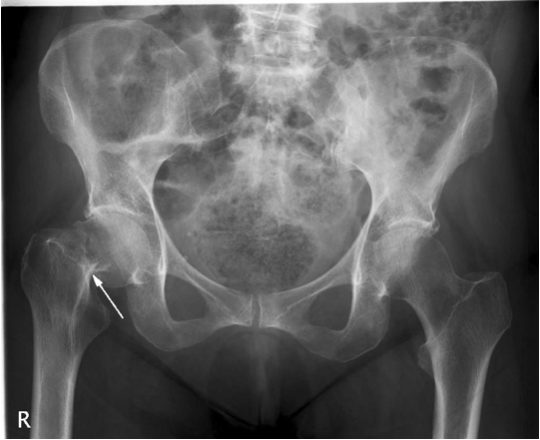

В ортопедии и травматологии рентгенологическое исследование используют для диагностики деформирующего коксартроза, артритов, асептического некроза головки бедренной кости, костных новообразований, вывихов, переломов шейки бедра и т. д. Рентгтенография позволяет подтвердить наличие патологии, но не всегда дает достаточно информации. Нельзя, например, получить послойное изображение тканей, из-за чего врачи не могут определить точную локализацию патологических изменений.

Симптомы и синдромы, которые выявляют с помощью рентгенографии:

- сужение суставной щели. Признак дистрофических изменений суставных хрящей. Этот симптом выявляют у больных с деформирующим остеоартрозом и хроническими артритами;

- остеопороз. Снижение плотности костей. Характеризуется уменьшением количества костных балок в единице объема костной ткани. Патология развивается в пожилом возрасте. Сам остеопороз протекает бессимптомно, но на его фоне зачастую развивается деформирующий остеоартроз и переломы шейки бедра;

- деструкция. Возникает вследствие инфекционного процесса. Характеризуется разрушением участков кости с их дальнейшим замещением гноем, грануляциями или опухолевой тканью. Наличие деструкции может указывать на парапротезную инфекцию, остеомиелит, злокачественные новообразования;

- некроз. Неинфекционное омертвение костной ткани. Чаще всего участки некроза появляются в области головки бедренной кости. Причина – возрастное ухудшение кровотока и обмена веществ.

Выявление того или иного признака на рентгенограмме косвенно указывает на определенную патологию. Часто для постановки диагноза врачу хватает данных анамнеза, осмотра и рентгенографического исследования.